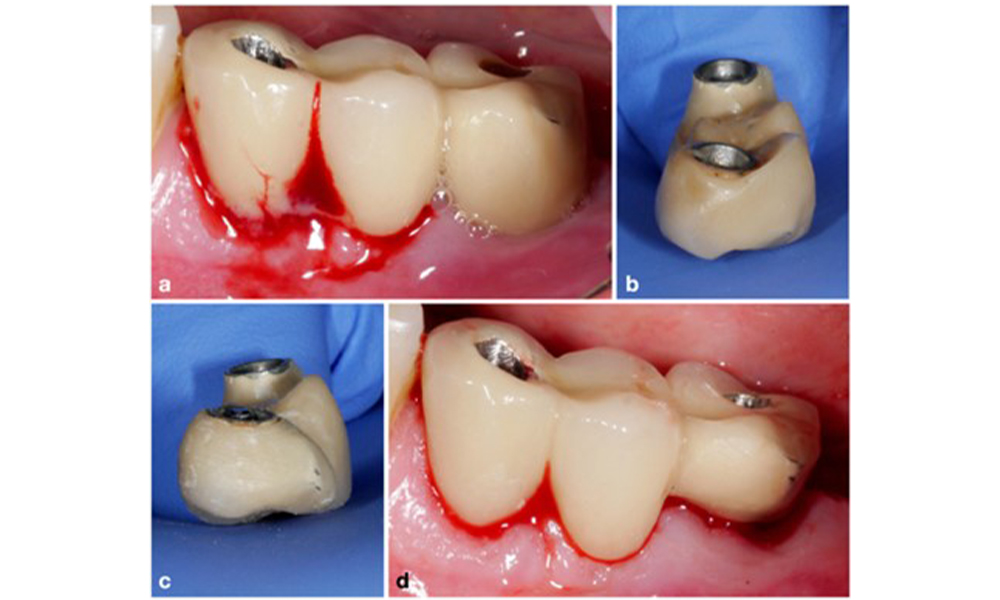

The World Workshop on the Classification of Periodontal and Peri‐Implant Diseases and Conditions from 2017 established diagnostic criteria for peri-implant mucositis and peri-implantitis (Renvert et al. 2018). Peri-implant mucositis is defined as (1) presence of inflammation around the implant (i.e., redness, swelling, line or drop of bleeding within 30 seconds of probing), combined with (2) no additional bone loss after initial healing (figure 1).

Peri-implantitis is identified by (1) signs of inflammation similar to mucositis, (2) radiographic evidence of bone loss after initial healing and (3) an increase in probing depth compared to measurements taken shortly after placing the prosthetic reconstruction (figure 2). In the absence of previous radiographs, radiographic bone level of ≥ 3 mm along with bleeding on probing and probing depths ≥ 6 mm, indicates peri‐implantitis.